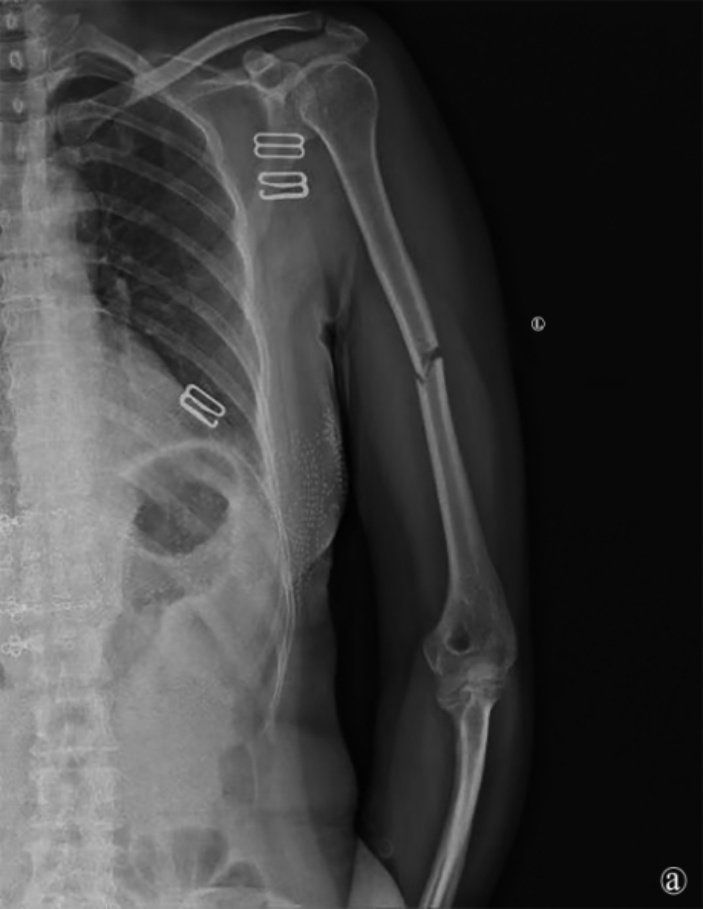

患者术后恢复顺利,无桡神经麻痹、切口感染、血管损伤等并发症。术后1天复查X线片示骨折解剖复位,内固定位置良好(图2)。术后第2天开始进行肩、肘关节被动功能锻炼,逐步过渡至主动活动。术后6个月随访X线片显示骨折线模糊,骨痂形成良好,内固定无松动、断裂(图3)。术后16个月返院拆除内固定装置,X线片示骨折愈合牢固,无畸形(图4)。拆除内固定前,手术切口愈合良好,瘢痕隐蔽,患者对外观满意(图5)。截至末次随访,患者肩关节平均主动前屈达165˚ ± 10˚,外展155˚ ± 12˚,内旋达到T8椎体水平;肘关节平均主动活动范围(屈–伸)为125˚ ± 15˚(屈曲140˚ ± 5˚,伸直15˚ ± 10˚),前臂平均旋前80˚ ± 5˚,旋后85˚ ± 5˚。采用标准化量表评估,患者平均DASH上肢功能障碍评分为12分 ± 5分,表明仅有轻度功能障碍;平均MEPS肘关节功能评分为92分 ± 6分,对应“优秀”等级。疼痛控制方面,术后平均静息态VAS疼痛评分为1.5分 ± 1.0分,活动时为2.5分 ± 1.5分,已恢复正常工作和生活。

Figure 2. Follow-up radiograph on postoperative day 1 shows satisfactory reduction of the fracture fragments

2. 术后1天复查X片示骨折断端复位良好